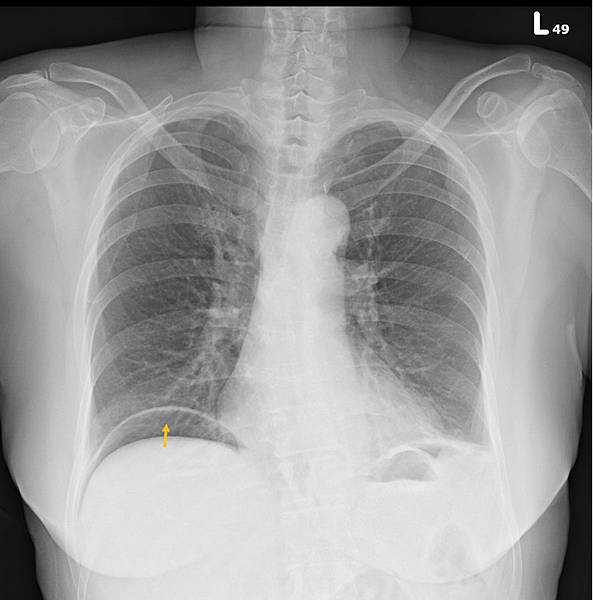

CXR才是診斷的經典:

右側橫膈下方有經典的Free air,

是胃/十二指腸或小腸或大腸破了!一個胃或腸的小破洞,電腦斷層無法判定哪兒破了,一般外科開下去發現是遠端降結腸(Distal descending colon)破了一個洞(0.5 cm),於是找直腸外科繼續完成手術。